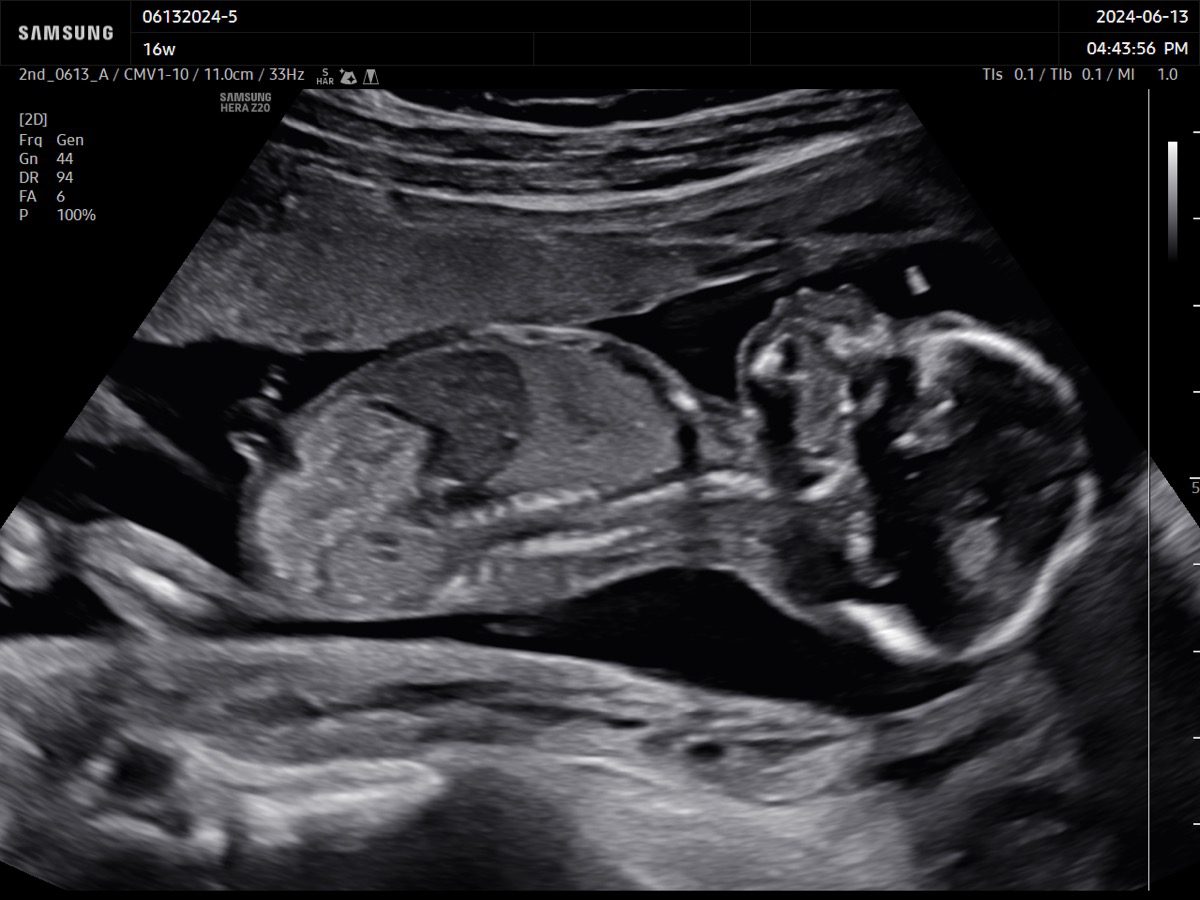

Comprehensive, advanced and expert MFM care for high-risk pregnancies

- Fetal anomalies